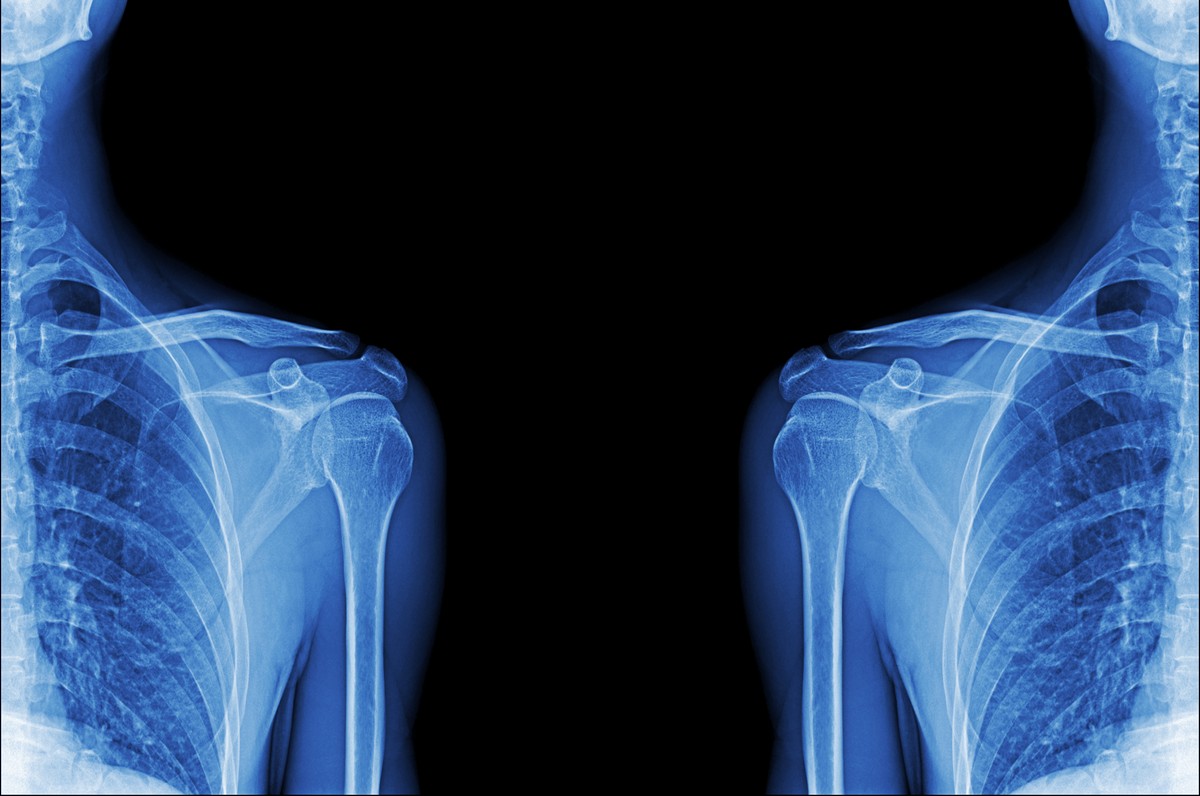

Благодаря своей анатомической сложности, плечевое сплетение часто подвергается различным патологическим процессам — травмам, компрессии, воспалениям и дегенеративным изменениям. Для полноценной диагностики состояния нервных корешков и оценки возможных патологий наиболее точным и информативным методом признана магнитно-резонансная томография (МРТ). Данный способ визуализации позволяет получить качественное изображение структуры нервных волокон, выявить патологические процессы. Это делает его незаменимым инструментом в нейрологии и травматологии.

Плечевое сплетение представляет собой объединение нервных волокон, образованное передними ветвями 4–8 шейных (C4–C8) и 1–2 грудных (Th1–Th2) спинномозговых нервов. Оно разделяется на стволы и пучки, которые дают начало коротким и длинным нервам, иннервирующимся в плечевой пояс и верхние конечности.

МРТ является современным методом визуализации, с помощью которого можно подробно исследовать анатомическое строение и патологические изменения нервных структур. Также это эффективный инструмент для оценки состояния корешков, стволов, пучков и конечных ветвей нервов.

Диагностическая процедура помогает выявлять компрессионные, воспалительные, дегенеративные или опухолевые процессы. С помощью МРТ врач может изучить межлестничный промежуток, крючковидную связку, подмышечную область и окружающие мягкиеткани. Это особенно важно при травмах, невралгиях и подозрениях на опухолевые образования.